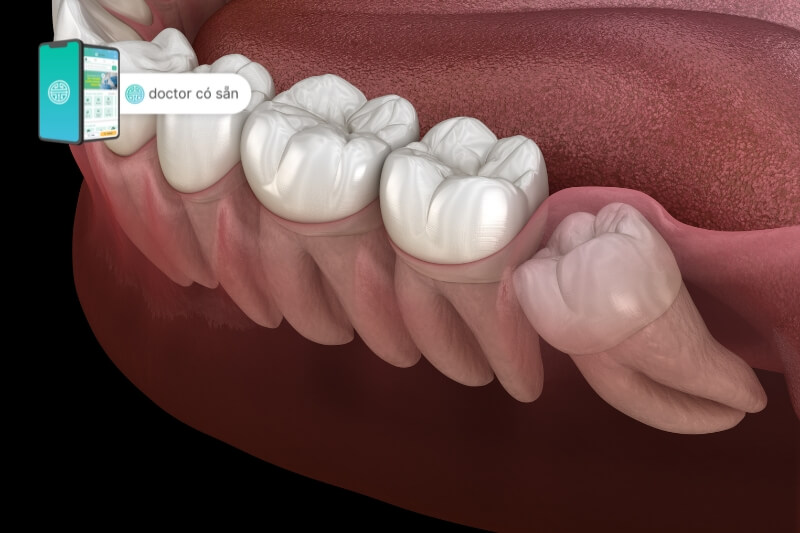

Lợi trùm là tình trạng mà phần lợi bao phủ lên bề mặt răng. Lợi trùm có thể bao phủ toàn bộ hoặc một phần răng. Thường khi răng mọc, phần này dần tiêu biến. Tuy nhiên, đôi khi lợi trùm có thể không tan, làm chặn sự phát triển của răng và gây đau. Lâu dài, khi răng tiếp tục mọc, nó có thể đẩy lợi trùm tạo khoảng trống dưới lợi. Nếu không chăm sóc và vệ sinh răng miệng thường xuyên, có thể dẫn đến viêm nhiễm và sưng của lợi.

Viêm lợi trùm còn được gọi là viêm nhiễm lợi trùm, là một vấn đề răng miệng thường xảy ra khi răng khôn bắt đầu mọc. Tình trạng này xuất phát từ việc phần lợi ở phía trong hàm bao phủ lên phần trên của răng khôn, làm cho răng bị kẹt lại và không thể phát triển một cách bình thường. Và không gian hẹp giữa lợi và răng khôn tạo điều kiện thuận lợi cho vi khuẩn và cặn thức ăn tích tụ, từ đó gây ra viêm nhiễm và các vấn đề khác.

- Lợi trùm là tình trạng mà phần lợi bao phủ bề mặt răng, có thể che kín hoặc chỉ một phần răng. Thường khi răng mọc, lợi sẽ tự tan, nhưng trong một số trường hợp, lợi trùm có thể ngăn cản sự phát triển của răng, gây đau cho bệnh nhân. Khi răng tiếp tục mọc, nó đẩy lợi trùm tạo ra khoảng trống dưới lợi. Nếu không vệ sinh răng miệng cẩn thận, có thể gây viêm và sưng.

- Một số trường hợp khi răng mọc, lợi không tiêu biến như thông thường. Thay vì nhường chỗ cho răng, lợi trùm cản trở và gây khó khăn cho răng phía dưới. Đầu răng nhọn đâm vào lợi và tạo ma sát liên tục, dẫn đến viêm, sưng và đau đớn trong vùng lợi.

- Răng mọc xô lệch: Răng khôn không thể mọc bình thường, gây xô lệch, khó khăn khi ăn nhai, ảnh hưởng đến tạo hình cắn và thẩm mỹ.